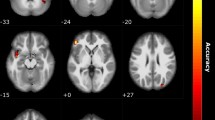

Next, we examined the link between genotype and the neural organization of ON in the olfaction cohort. Local intrinsic networks are usually organized into correspondent stimulus- or task-induced cortical representations33; therefore, we defined bilateral piriform cortices as anatomical ON seed areas centered at MNI coordinates (− 22, 0, − 14) and (22, 2, − 12), based on a meta-analysis of olfactory activation fMRI studies34. We performed whole-brain seed-based analysis of rs-fMRI to identify brain regions exhibiting genotypic differences in intrinsic connectivity for olfactory perception. Age and gonadal hormonal levels (estrogen, progesterone, and testosterone) were regressed out as nuisances. Between-group differences in ON connectivity were observed only between Met/Met vs. Val/Val groups. No significant finding was observed in other pairwise comparisons (i.e. Met/Met vs. Val/Met or Val/Met vs. Val/Val). The ON in the Met/Met group presented an additional spatial dimension spanning the inferior temporal gyrus (ITG, BA20), middle temporal gyrus (MTG, BA21), PCC (BA23) and RSC (BA30; Fig. 2A), indicating the engagement of semantic memory system to augment odor identification35. In addition, the ON in Met/Met group was shown to engage multiple sensory systems, including the visual (superior occipital lobule, SOL, BA19), somatosensory (postcentral gyrus, PostCG, BA3/1/2), and gustatory (insula, INS, BA13) areas (Fig. 2A). The cross-modal incorporation of contextual information associated with previous sensory experience can help to identify specific odors through the recollection of stored images31. Note that the FCs identified in this analysis exhibited a dosage-dependent effect of the Met allele (Fig. 2B and Table 1), where the odor-identification performance shows a cohesive trend with the Met-allele dosage-dependent neural wiring (Fig. 1C). However, the correlations between FCs of ON and odor-identification performance did not achieve statistical significance. To sum up, olfactory performance and brain imaging findings both strongly suggest that the superior odor-identification performance of Met/Met subjects can be attributed to the engagement of semantic memory and multiple sensory cortices within ON.

Representations of BDNF gene-informed piriform cortex (PC)-seeded olfactory network (olfaction cohort, n = 47). (A) The between-group comparison of olfactory networks in the Met/Met and Val/Val group exhibited stronger links to the semantic (middle/inferior temporal gyrus, MTG/ITG) and autobiographical (retrosplenial cortex, RSC; posterior cingulate cortex, PCC) memory areas, visual cortex (superior occipital lobule, SOL), gustatory area (insula, INS) and somatosensory area (postcentral gyrus, PostCG). (B) Met-allele dosage effect on the PC-seeded functional connectivity (FC). Note that in the linear regression model, Met/Met was defined as “2”, Val/Met as “1”, and Val/Val as “0”. The peak coordinates and the linear regression results for the Met-allele dosage effect can be found in Table 1.